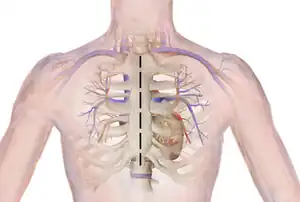

Median sternotomy is a type of surgical procedure in which a vertical inline incision is made along the sternum, after which the sternum itself is divided using a sternal saw.[1] This procedure provides access to the heart and lungs for surgical procedures such as heart transplant, lung transplant, corrective surgery for congenital heart defects, or coronary artery bypass surgery.[2][3][4]